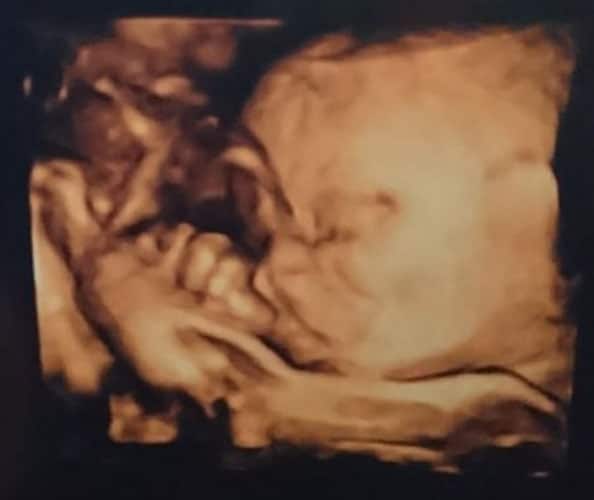

Ultraschallbilder aus dem 3. Trimester (29. bis 40. SSW)

Im dritten Trimester der Schwangerschaft ist das Baby so groß, dass es nicht mehr komplett auf ein Ultraschallbild passt. Nun kann man wunderbare 3D-Ultraschalle des Gesichts machen. In diesem Semester nehmen die Babys nochmal rasant zu und wer Glück hat, kann auf seinem Ultraschall schon erste Gesichtszüge erkennen.

Was genau man auf einem Ultraschallbild erkennen kann, hängt nicht nur von der Größe des Babys ab, sondern auch davon wie gut das Ultraschall-Gerät ist, mit dem die Aufnahme gemacht wurde. Auch auf den Ultraschallbildern hier kannst du sehen, dass die Qualität stark schwankt. In der Regel kann man gut den Kopf und RUmpf des Babys erkennen und auch die Gliedmaßen erkennt man selbst als Laie gut.

Wer sich jedoch erhofft Gesichtszüge zu erkennen, der wird oft enttäuscht. Zwar kann man beim 3D-Ultraschall schon eine Menge sehen, aber das umgebende Fruchtwasser sorgt in den allermeisten Fällen für starke Störungen.